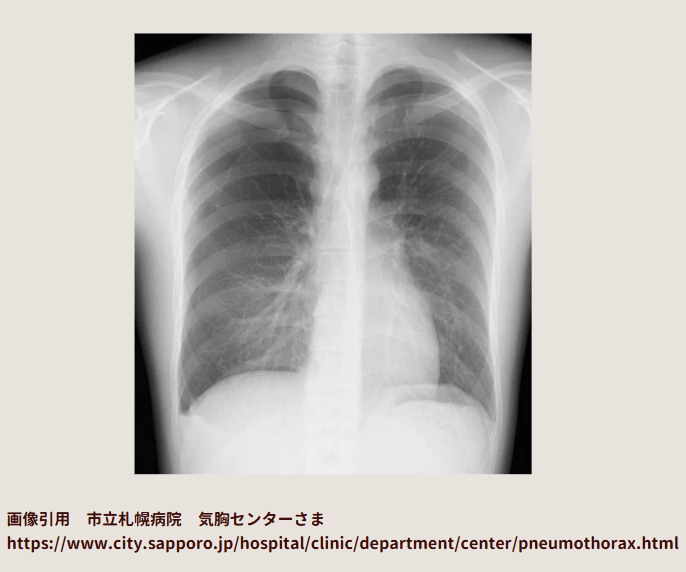

正常な胸部レントゲン画像

胸部レントゲン画像は、こっちを向いて立っている人を透視しているイメージなので、右肺と左肺は図のようになります。これを覚えて、「右肺に気胸があります」とか「左肺に気胸があります」とか言えるとかっこいいです。真ん中の白いのは心臓です。